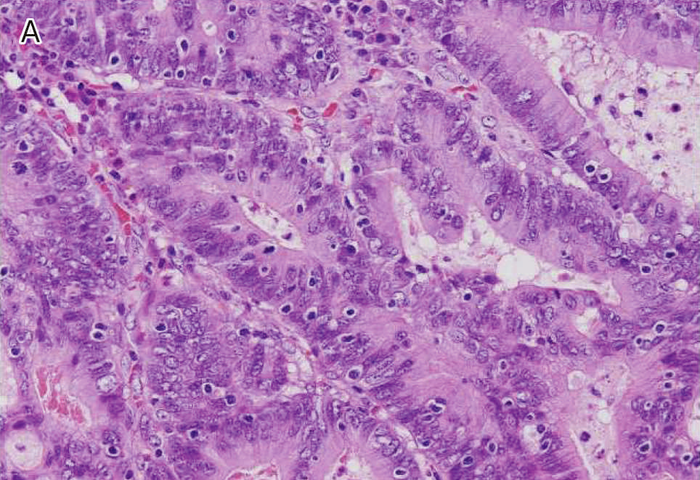

Ⅲ-2-1-2 ミスマッチ修復(MMR)異常を示す大腸癌に特徴的な病理組織学的所見

- MMR異常を示す大腸癌ではその他の大腸癌と比べ,いくつかの組織学的特徴が,より高頻度に認められる。改訂Bethesdaガイドライン28においては,①腫瘍内リンパ球浸潤

(tumor infiltrating lymphocytes:TIL),②髄様増殖,③粘液癌・印環細胞癌様分化,④Crohn様リンパ球反応(Crohn’s-like lymphocytic reaction)の4項目が挙げられている(図Ⅲ-3)。ただし,これらの病理組織学的特徴は必ずしもリンチ症候群に特有のものではなく,散発性MMR異常大腸癌にも共通して認められる58)。

図Ⅲ-3 MSI-High大腸癌の病理組織学的特徴

| A: | 腫瘍内リンパ球浸潤。腫瘍上皮内にhaloを伴ったリンパ球浸潤を認める。 |

| B: | 髄様増殖。腫瘍細胞は腺管を形成せず,充実性胞巣状の増殖を示す。 |

| C: | 粘液癌。多量の細胞外粘液を伴う。 |

| D: | Crohn様リンパ球反応。腫瘍周囲に多数のリンパ球の集簇巣を認める。 |